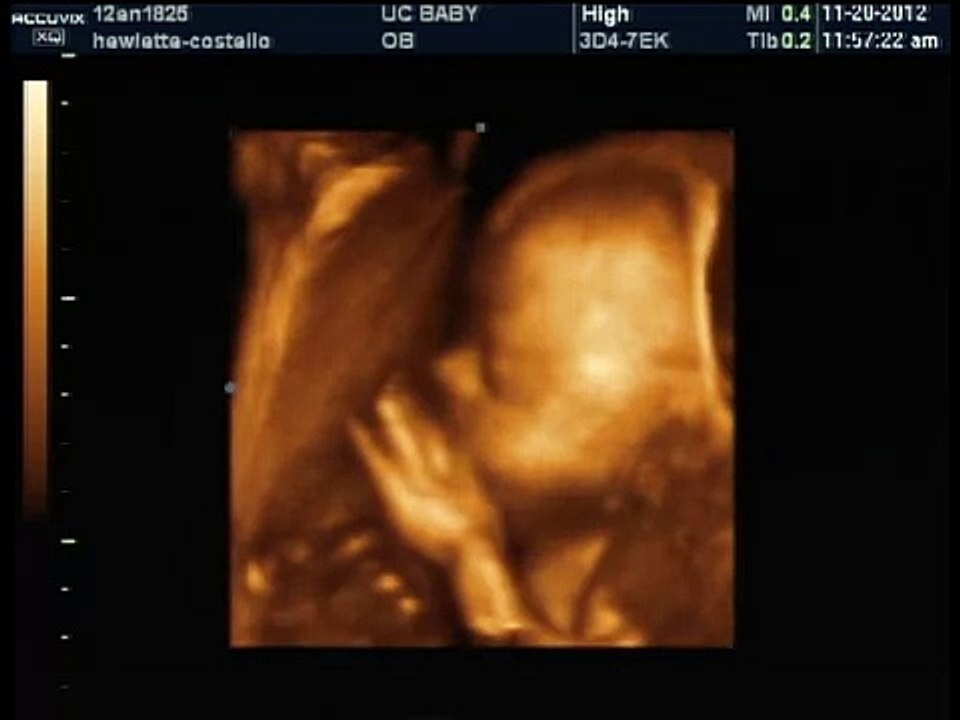

Baby boys heart beat 25 weeks 3d ultrasound nov 20 2012 video Dailymotion Boy Heart Beat In Womb Some babies have heart rates that are. one of the most universal myths about gender revolves around your baby’s heart rate. Your right breast is bigger than your left. You look at yourself in the mirror for at least a minute and your pupils dilate. You didn't suffer from morning sickness in your first trimester. a fetus’s heart. Boy Heart Beat In Womb.